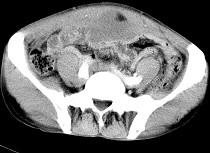

问题 男,56岁,无规律上腹痛,左锁骨上淋巴结肿大,消瘦、乏力,影像检查如图,最可能的诊断是 ( )

选项 A.腹膜结核 B.胃溃疡穿孔 C.胃癌并盆腔种植 D.胃及腹腔淋巴瘤 E.肠系膜淋巴管瘤

答案 C